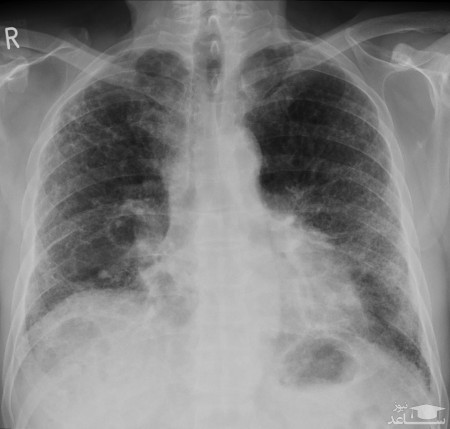

محققان اعلام کردند از بین ۷۰ بیمار بهبودیافته، در سی تی اسکن ۶۶ مورد از آن ها آسیب به ریه مشاهده شده است.

از ۹۰ بیمار مبتلا به کرونا که در بیمارستان Huazhong بستری شده بودند، در ۷۵ مورد آن ها از تاریخ ۱۶ ژانویه تا ۱۷ فوریه، آسیب در هر دو ریه مشاهده شده بود.

سی تی اسکنی که از قبل ترخیص از ۷۰ بیمار گرفته شد، نشان داد که ۴۲ مورد این بیماران دارای ضایعات در اطراف آلوئول ها هستند که احتمالاً این ضایعات به زخم تبدیل می شود.